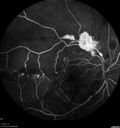

BRVO Macular Non Perfusion

brvocme_lomo_28229.png

9 files, last one added on Dec 02, 2010

Album viewed 876 times